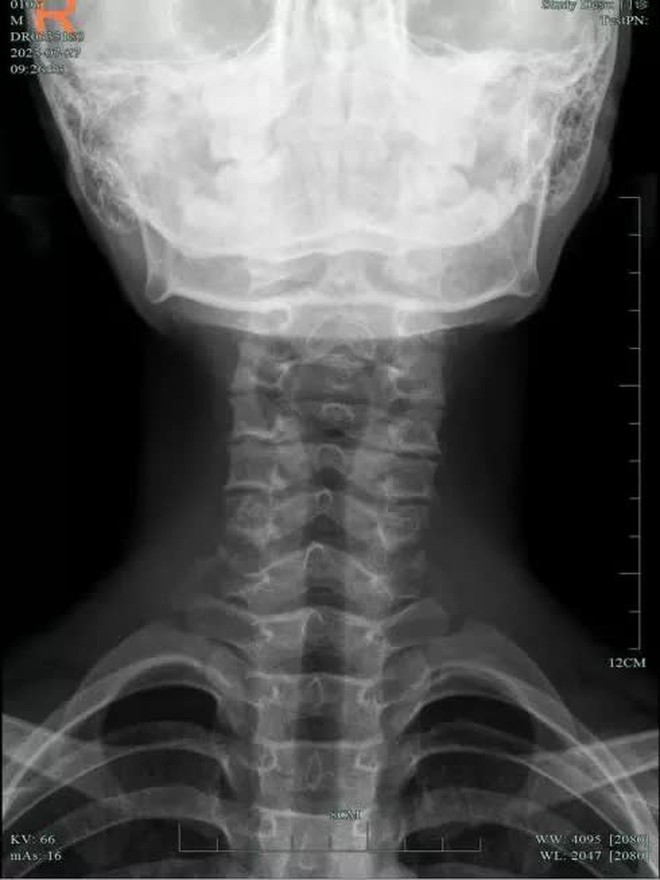

Bác sĩ phán đoán sơ bộ rằng Tiểu Chiêu có vấn đề về cột sống cổ. Kết quả khám phim DR vùng cổ cho thấy bệnh thoái hóa đốt sống cổ của cậu bé rất nghiêm trọng, thậm chí còn nghiêm trọng hơn tình trạng của nhiều người lớn. Cột sống cổ của cậu bé lúc này tương đương với 1 người ở độ tuổi 30.